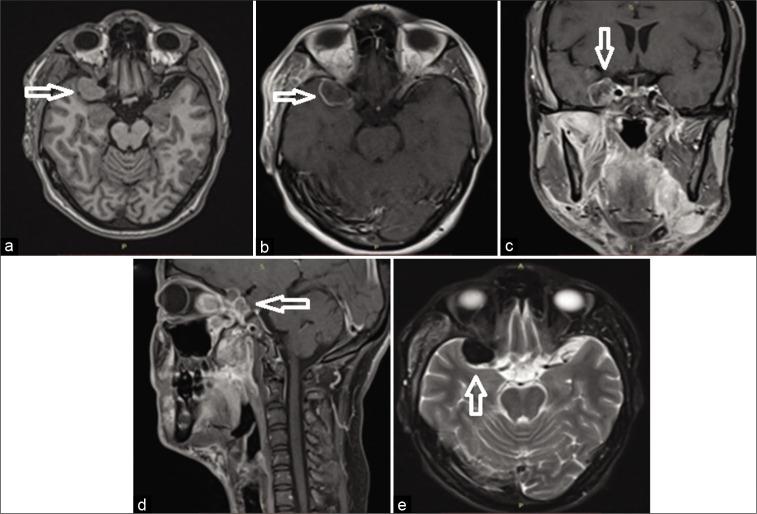

We present our experience with a biopsy-proven case of IgG4-RD presenting with an intracranial extradural tumor-like mass infiltrating the temporal lobe. The patient was treated with high doses of corticosteroids followed by slow tapering. The neurological manifestations gradually improved and resolved after 2 months with a cerebral MRI showing a significant reduction in the tumoral size.

我们报告一例经活检证实的IgG4-RD病例,该病例表现为颅内硬膜外肿瘤样肿块浸润颞叶。患者接受了高剂量皮质类固醇治疗,随后缓慢减量。2个月后,神经系统表现逐渐改善并消失,脑部MRI显示肿瘤大小显著缩小。